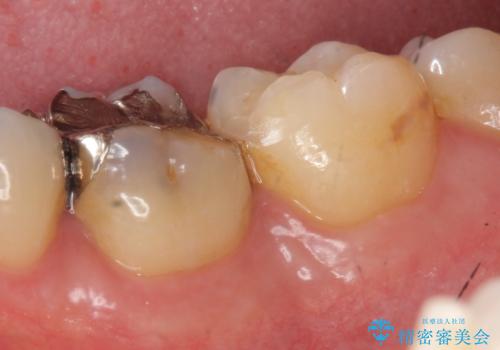

銀歯の下の虫歯|オールセラミッククラウン

担当医 河野豊嘉